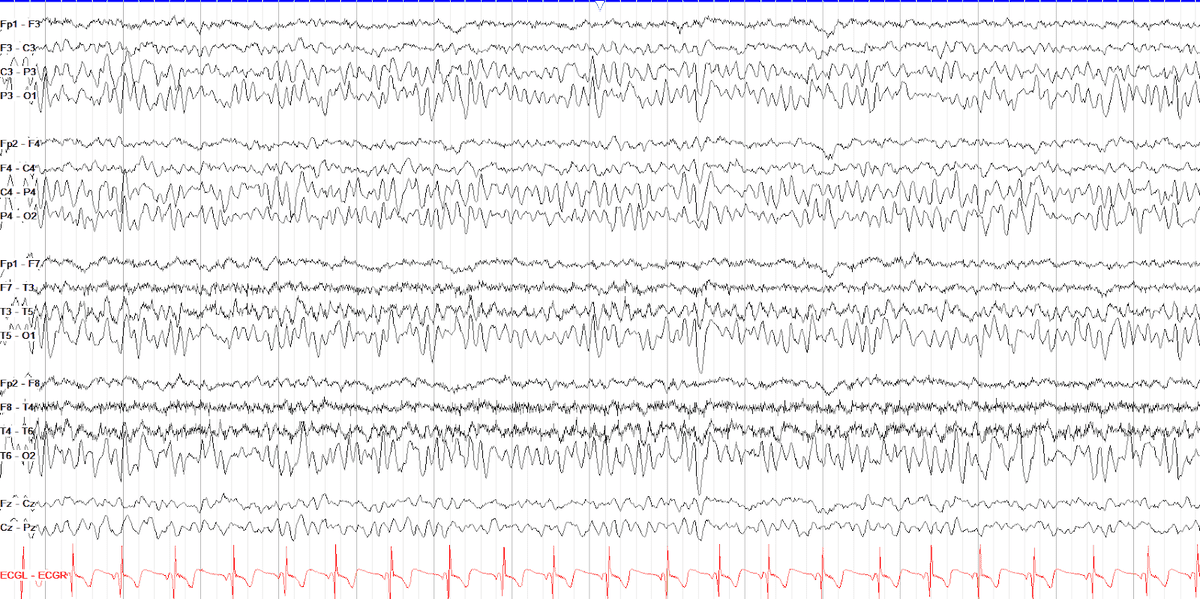

In children delta activity is common especially in the posterior head region. These physiological slow waves usually occur singly and randomly with intermixed alpha rhythm. The waveform resembles the “sail” of a sail boat, this has sometimes been referred to as a “sail wave.” PSWY are more abundant in younger children. The “posterior slow wave of youth” becomes progressively less prevalent toward the age of 20 years but could be seen as late as 25 years of age. The posterior slow waves of youth are uncommon in children less than 2 years old and become maximum between ages 9 and 14. They are not always symmetric or synchronous between the left and right occipital electrodes and tend to be greater in amplitude and incidence on the right side. They may be more prominent during the early portion of the recording and tend to diminish toward the end of recording.

With increasing age, the alpha rhythm becomes more persistent, but there is underlying delta activity with a superimposed alpha or theta rhythm or intermittent delta activity interrupting the alpha rhythm (posterior slow waves of youth) (see Figs. 7-5 to 7-7 and 7-25). The amplitude may reach 100 to 150 μV (measured at the occipital electrode with an ipsilateral ear reference). During the eyes-open state, the background activity is slower, consisting of an irregular delta–theta pattern (see Fig. 7-11). It is important to assess the background activity while the subject’s eyes are closed, but during the fully awake state. If the subject is too young or mentally challenged and unable to follow the technologist’s commands, eyes closed for 20 to 30 seconds must be recorded by the technologist holding the eyes closed. When the alpha rhythm reaches 10 Hz at about 15 years of age, underlying delta activity and posterior slow waves of youth diminish, and the amplitude becomes close to the adult range (40 to 60 μV) (see Figs. 7-7 and 7-8). In children and adolescents, frontocentral activity may be dominated by theta rhythm despite well-defined and dominant alpha rhythm posteriorly (see Fig. 7-23).